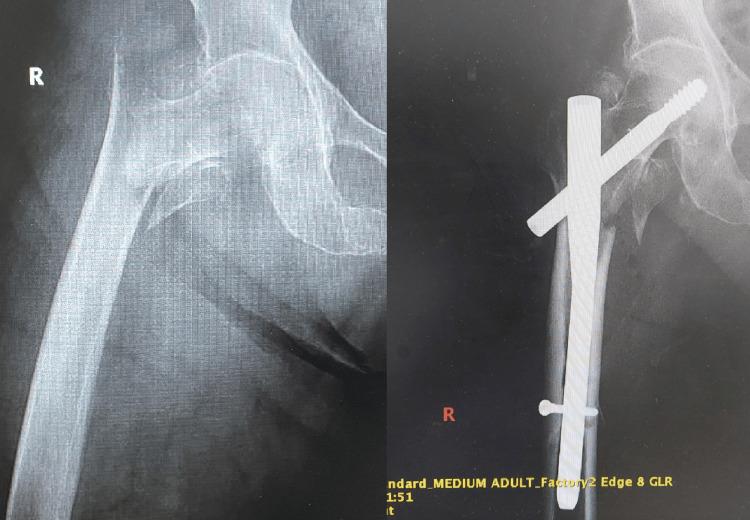

Managing osteoporotic fractures in older individuals is a difficult task in orthopedic surgery. It requires a careful approach that combines advanced diagnostic methods, customized surgical treatments, and comprehensive rehabilitation strategies. This article presents the results of an analysis carried out at the University Emergency Hospital, Bucharest. The analysis specifically examines the treatment of osteoporotic fractures using different osteosynthesis techniques. Although diagnostic tools like dual-energy X-ray absorptiometry (DXA) and Fracture Risk Assessment Tool (FRAX) have improved, a considerable number of fractures still happen in people who do not have obvious osteoporosis. This emphasizes the importance of using additional diagnostic measures such as high-resolution peripheral quantitative computed tomography (HR-pQCT) and quantitative computed tomography (QCT) to improve the accuracy of predictions. The study demonstrates the intricate nature of surgical decision-making and the significance of adjusting techniques to meet the specific needs of each patient. An instance of osteosynthesis failure resulting from the inappropriate choice of method highlighted the crucial significance of a thorough preoperative assessment. The discussion highlights the importance of early mobilization and rehabilitation in reducing the risks associated with prolonged immobilization and improving patient recovery. This paper strongly supports the use of evidence-based and patient-centered methods in the management of osteoporotic fractures. It emphasizes the importance of utilizing the most recent advancements in diagnostic and surgical technologies. Promising advancements in orthopedic medicine lie in the future, particularly in the integration of interdisciplinary research and personalized medicine. These advancements have the potential to enhance patient outcomes in this population that is at high risk.

在老年个体中处理骨质疏松性骨折是骨科手术中的一项艰巨任务。这需要一种谨慎的方法,将先进的诊断方法、定制的手术治疗和全面的康复策略结合起来。本文介绍了在布加勒斯特大学急诊医院进行的一项分析结果。该分析具体研究了使用不同骨固定技术治疗骨质疏松性骨折的情况。尽管双能X线吸收法(DXA)和骨折风险评估工具(FRAX)等诊断工具有所改进,但在没有明显骨质疏松的人群中仍有相当数量的骨折发生。这强调了使用高分辨率外周定量计算机断层扫描(HR-pQCT)和定量计算机断层扫描(QCT)等额外诊断措施以提高预测准确性的重要性。该研究证明了手术决策的复杂性以及根据每个患者的具体需求调整技术的重要性。因方法选择不当导致骨固定失败的一个实例突出了全面术前评估的关键意义。讨论强调了早期活动和康复在降低与长期固定相关的风险以及改善患者恢复方面的重要性。本文强烈支持在骨质疏松性骨折管理中使用基于证据和以患者为中心的方法。它强调了利用诊断和手术技术最新进展的重要性。骨科医学未来有充满希望的进展,特别是在跨学科研究和个性化医学的整合方面。这些进展有可能改善这一高危人群的患者预后。